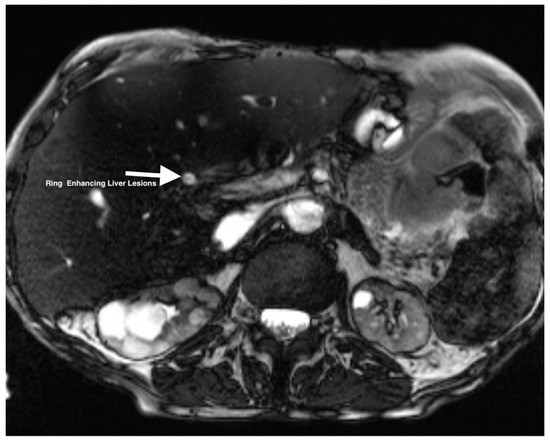

The patient was a 62-year-old woman with a history of Roux-en-Y gastric bypass (1993) for weight management, liver cirrhosis, and chronic kidney disease stage IV secondary to apolipoprotein A-1 amyloidosis requiring simultaneous liver–kidney transplant with gastrostomy tube placement in the remnant pouch due to severe malnutrition (4 months before presentation), chronic iron deficiency anemia with unremarkable EGD, and colonoscopy before transplant (baseline Hb: 8 mg/dL). The patient had persistently elevated liver enzymes post-transplant and was admitted to the hospital for evaluation. The workup revealed multiple ring-enhancing liver lesions and focal narrowing at the anastomotic site, with extra- and intrahepatic duct dilatation on magnetic resonance cholangiopancreatography (Figure 1). In order to address the focal narrowing and the dilatation of the extra and intrahepatic duct, she underwent endoscopic retrograde cholangiopancreatography (ERCP) and endoscopic ultrasound (EUS) through the G-tube, which was unsuccessful due to significant fibrosis of the tract. Subsequently, a stent was placed to dilate the tract. A repeat ERCP and EUS through the G-tube showed right-sided structuring and dilatation. An attempt was made to biopsy the areas of ring-enhancing lesions during the EUS; however, it was unsuccessful due to poor visualization of the hepatic lobes. Subsequently, an IR-guided liver biopsy was attempted, but the histopathologic evaluation was inconclusive due to the limited sample. The patient was eventually discharged with close outpatient follow-up and monitoring.

Figure 1. MRI of the abdomen showing ring-enhancing lesions in the liver.